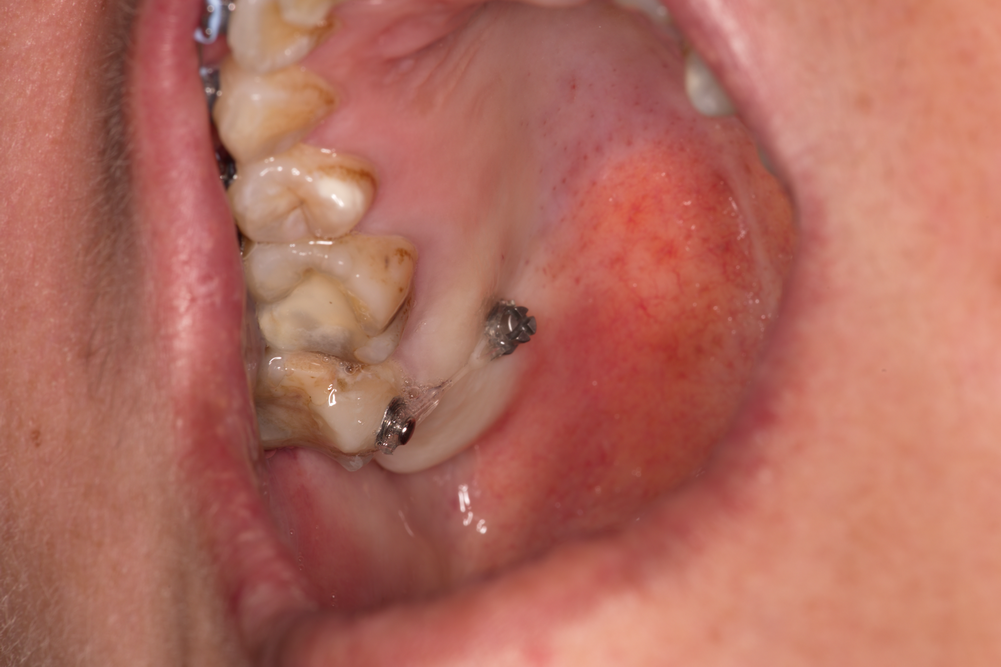

Зъбни импланти с натрупвания на плака и зъбен камък - налице е изразено остро възпаление. В рамките на три дни се формира структурирана зъбна плака, която е особено агресивна - в нейния обем започват да се размножават аеробни и анаеробни микроорганизми, които са основният причнител на зъбния кариес и пародонтита. При периимплантита (възпаление на тъканите около зъбния имплант) положението е същото - наличието на зъбна плака е основен етиологичен фактор. Това налага старателно почистване на надлигавичните елементи както от страна на пациента, така и професионално - от страна на зъболекаря. Колкото е по-грапава една повърхност, толкова повече плака задържа тя и толкова по-трудно става нейното почистване - поради което наистина зъбните импланти с полирана повърхност развиват периимплантити статистически доста по-рядко. Проблемът е че възпалението на околоимплантатните тъкани е полиетиологичен процес - предизвиква се от много и различни фактори, а и зъбна плака е възможно да се задържи дори и върху идеално полирана повърхност. Награпавената имплантатна повърхност е по-добре да бъде разположена интраосално, което в крайна сметка е идеята на дизайна на вътрекостния имплант; при невъзможност за това се налага извършването на костни аугментационни процедури, които изискват допълнително познания и повишено внимание по време на работа. На горната снимка освен това се виждат обилни натрупвания върху цикатризиращите винтове (сулкусформери) - те са полирани, и то при производствени, а не при клинични или лабораторни условия. Зъбната плака и зъбният камък обаче са налице - което е очевиден пропуск от страна на пациента.

При горния клиничен случай се вижда и едно особено неприятно постоперативно усложнение - дехисценцията на оперативната рана. Статистически тя се наблюдава много по-често при поставянето на цикатризиращи винтове върху имплантатната платформа в сравнение с поставянето само на покривни винтове. Тази тенденция се обяснява с формирането на голям брой фиброзни мостчета между срещулежащите ламба - синтезираните съединителнотъканни влакна са механична пречка за отварянето на оперативната рана, което именно представлява дехисценцията. Наличието на гингивални оформители (сулкусформери) пречи на фиксацията на двете раневи повърхности една към друга и вероятността от дехисценция нараства значително. Колкото по-голям е размерът на ламбата и особено дълбочината на отпрепариране, толкова по-вероятно е да се отвори и оперативната рана. Обикновено това се случва на осми - десети ден след поставянето на шевовете - когато започне синтез на съединителна тъкан в дълбочина и съответно придърпване на лигавицата и периоста в трите пространствени иземрения. Значение за дехиценцията има и хирургичната техника при подготовката на ламбото - необходимо е адекватното освобождаване на меките тъкани и срязването на различните мускулни инсерции, които биха могли да придърпват ламбата по време на оздравителния период. Много често се налага така нареченият облекчителен разрез - срязване на периоста в дълбочина, успоредно на основния лигавиченр азрез, при което подвижността на ламбото рязко се увеличава. При ротация на тъканите с цел каквото и да е пластично затваряне на раната вероятността от формиране на дехисценции рязко нараства; това се наблюдава особено често при орални хирурзи с недостатъчен клиничен опит, тъй като те имат повече психологически задръжки по отношение на отпрепарирането на по-големи по размер ламба. Най-добре е при пускане на меките тъкани върху оперативното поле те да застват в желаното пространствено положение пасивно, без да се налага силова адаптация и притискане с инструмент - това гарантира профилактиката на дехисценциите. Така нареченият двуслоен шев адаптира периост срещу периост и това също води до рязко снижаване на честотата на дехисценциите. При всички случаи старателното обшиване с много на брой конци е желателно - в лицево - челюстната област на практика не съществува ограничения в броя на поставените конци на линеен милиметър, тъй като кръвоснабдяването на областта е отлично и исхемизация на тъканите е на практика невъзможна.

При горния случай има съчетание на два неблагоприятни фактора -

недостатъчна орална хигиена

и дехисценция на оперативната рана. При такова положение вероятността от провал

в лечението нараства значително - което и се случи около 3 седмици след

поставянето на имплантите. Съчетаването на два или повече рискови фактора е от

особено значение за всички усложнения в медицината - от най-безобидните до

животозастрашаващите. Това следва да се има предвид при планирането и

оперативното изпълнение на всеки един клиничен случай. Важни са и

постоперативното наблюдение и адекватните грижи за раната. В никакъв случай не

бива да се отпрепарират вторични ламба и да се поставят фиксиращи шевове - това

няма да доведе до корекция и формиране на епителна бариера, а само ще увеличи

площта на дехисценцията и всичко ще изглежда още по-зле след 10 - 14 дни.